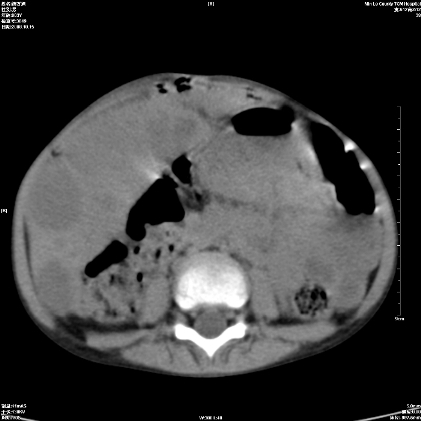

标题: PED1609:男性,3岁。彩超示肝Ca. [打印本页]

标题: PED1609:男性,3岁。彩超示肝Ca.

3岁;肝低密度灶;有钙化;有转移灶;考虑肝母细胞瘤;查afp

支持肝母细胞瘤肝内转移

考虑神经母细胞瘤并肝转移